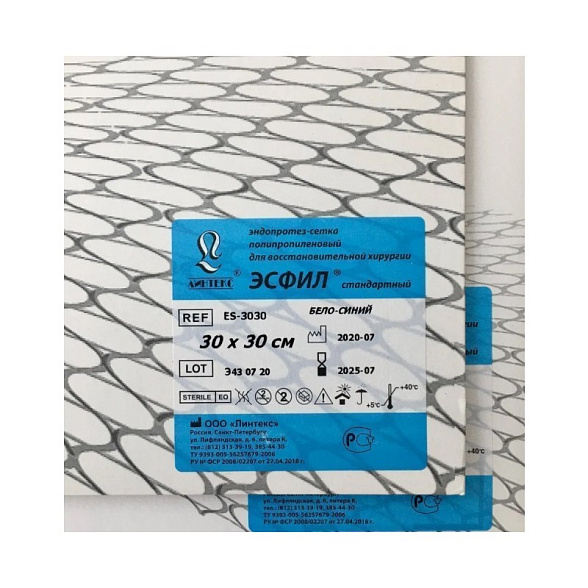

Эндопротез-сетка (сетка хирургическая) полипропиленовый для восстановительной хирургии ЭСФИЛ стандартный, 30х30 см, Линтекс

Эндопротез-сетка полипропиленовая ЭСФИЛ стандартная 30х30 см (Линтекс)

| Наименование товара | Эндопротез-сетка хирургическая полипропиленовая ЭСФИЛ |

| Тип | Стандартная, нержавеющая |

| Бренд / Производитель | Линтекс (Lintex), Россия |

| Размер | 30 см x 30 см |

| Стерилизация | Изделие поставляется стерильным (обычно методом ЭОГ — окисью этилена или радиационным) |

| Упаковка | Индивидуальная двойная: внутренний стерильный чехол и внешняя защитная упаковка. |